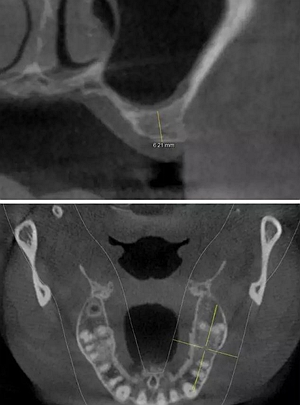

術(shù)前CBCT檢查

骨高度不足,內(nèi)提升的適應(yīng)癥??梢?jiàn)竇膜致密,厚度均勻。骨高度不足,骨寬度尚可。

術(shù)后CBCT